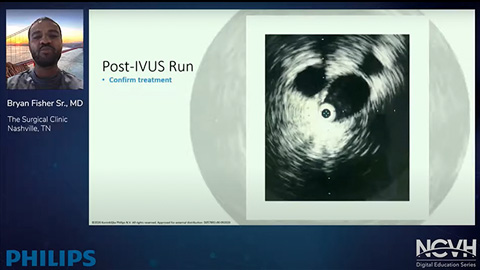

Catéteres para imagenología periférica

Nuestros catéteres para imagenología periférica de imagen ayudan a determinar la localización de la morfología de la enfermedad y de la lesión, incluyendo calcio y trombo. IVUS también se puede utilizar para dimensionar adecuadamente los stents y confirmar la integridad del tratamiento.